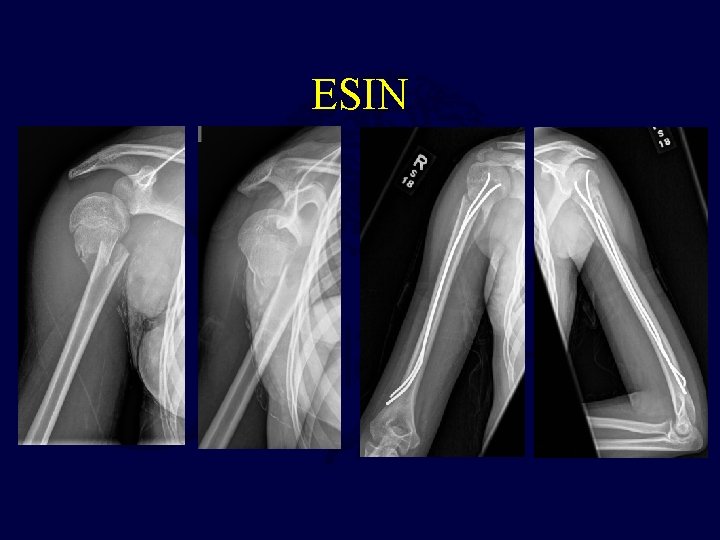

Elastic Stable Intramedullary Nails • More recently proposed form of fixation • Avoid morbidity of percutaneous pins – Soft tissue irritation – Migration • Requires repeat anesthetic for removal

ESIN

Intramedullary Nailing Versus Percutaneous Pin Fixation • • 50 pts 27 pts with percutaneous pins 23 pts with IMN’s IMN group – slightly lower angulaton, longer operative times, increased EBL, more second surgeries, but lower complication rate • Both treatments effective and decision made on surgeon familiarity with implants Hutchinson et al. Intramedullary Nailing Versus Percutaneous Pin Fixation of Pediatric Proximal Humerus Fractures: A Comparison of Complications and Early Radiographic Results. JPO. 2011; 31: 617 -622.